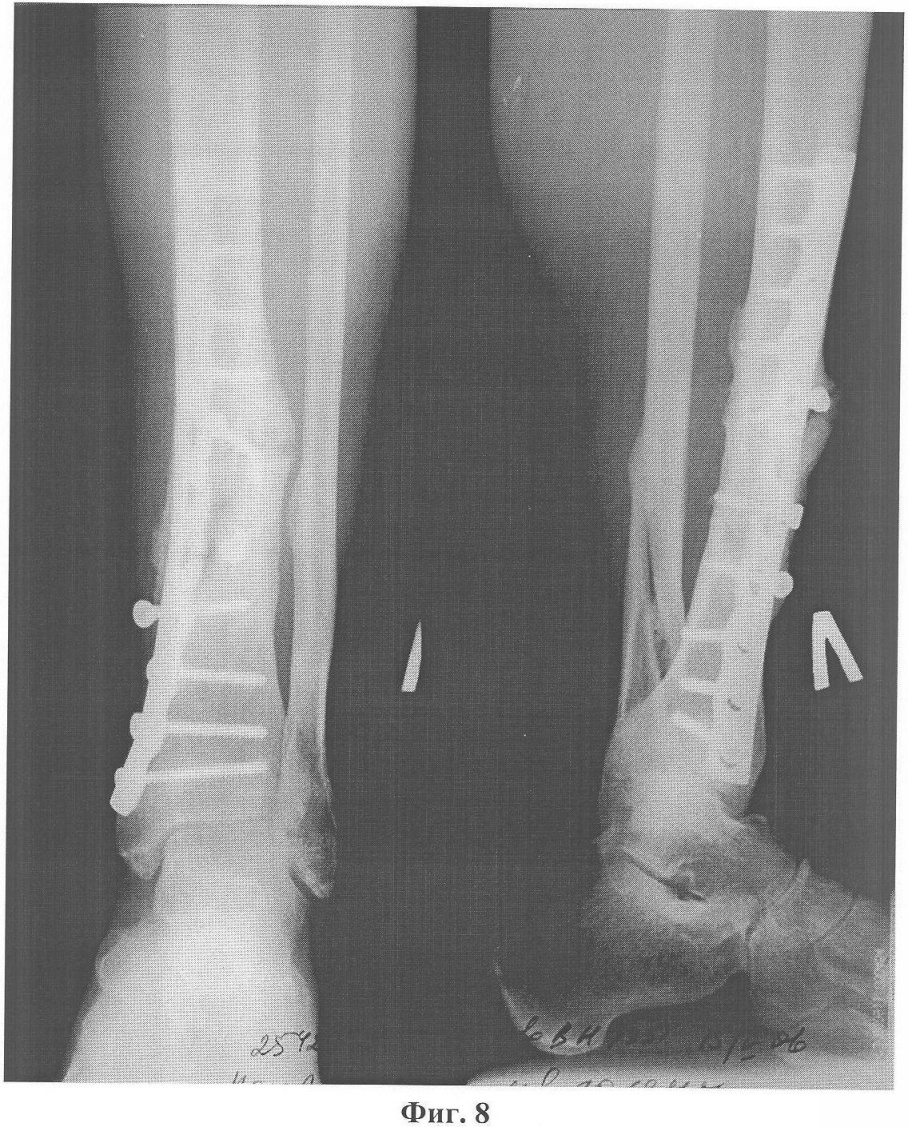

Фиг.8. Ложный сустав большеберцовой кости левой голени с переломом накостной металлоконструкции и миграцией винтов.

Больной Н., 55 лет, 23 июня 2005 года в результате бытовой травмы получил закрытый оскольчатый перелом обеих костей левой голени. Доставлен в городскую клиническую больницу г.Москвы, где был произведен остеосинтез большеберцовой кости левой голени пластиной АО с ограниченным контактом. Послеоперационный период протекал без осложнений. Проведено восстановительное лечение, включающее ходьбу с костылями с дозированной, постепенно увеличивающейся нагрузкой на оперированную конечность. Через 3 месяца после операции начал ходить с палочкой с полной нагрузкой на левую стопу. Однако при ходьбе отмечал умеренные боли в области перелома. Динамический рентгеноконтроль демонстрировал замедленную консолидацию перелома большеберцовой кости на фоне сросшегося перелома малоберцовой кости. В мае 2006 года боли в голени при ходьбе усилились. При контрольной рентгенографии обнаружен ложный сустав большеберцовой кости с переломом накостной металлоконструкции и миграцией винтов (фиг.8). 6 июня 2006 года под общим обезболиванием сломанная пластина была удалена с выполнением операции на ложном суставе по разработанному способу (фиг.9). После снятия швов и ликвидации отека произведена иммобилизация конечности укороченной циркулярной повязкой Scotchcast (до коленного сустава), и больной приступил к нагрузке в дозированном режиме. К концу 3-го месяца ходьба с полной нагрузкой без дополнительной опоры (фиг.10) в иммобилизирующей повязке (фиг.11), болей в голени нет, повязка снята, рентгенологически определяется сращение перелома большеберцовой кости (фиг.12). После проведения 2-х недельного реабилитационного курса функция конечности восстановлена в полном объеме (фиг.13, 14).